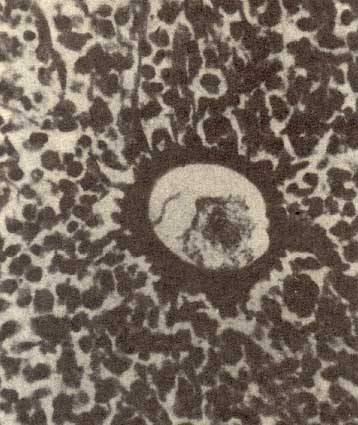

裂体吸虫